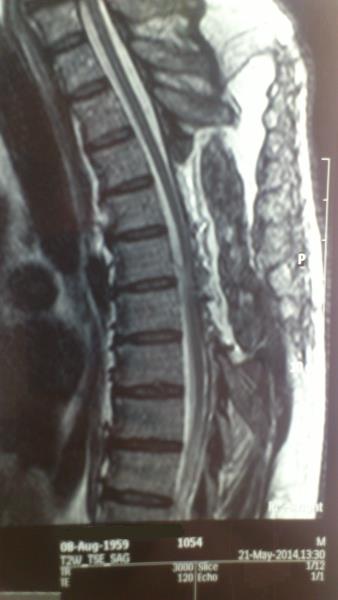

Ασθενής άνδρας 54 ετών με ιστορικό μυϊκής αδυναμίας και αισθήματος αιμωδιών κάτω άκρων από 4ετίας με προοδευτική επιδείνωση και εμφάνιση επιπροσθέτως διαταραχών σφιγκτήρων  παραπέμφθηκε στην κλινική μας μετά από τη διενέργεια MRI ΘΜΣΣ που ανέδειξε εικόνα πρόσθιας κήλης νωτιαίου μυελού στο επίπεδο Θ5-Θ6. Ο ασθενής υποβλήθηκε σε οπίσθια προσπέλαση. Μετά από διατομή αμφοτερόπλευρα των οδοντωτών συνδέσμων και της ραχιαίας αριστερής Θ5 ρίζας αναγνωρίσθηκε πρόσθια κήλη του νωτιαίου μυελού μέσα από έλλειμμα οπισθίου πέταλου διπλής (duplicate ) κοιλιακής (ventral) σκληράς μήνιγγας.Με μικροχειρουργική τεχνική επιτεύχθηκε διεύρυνση του ελλείμματος με αφαίρεση του οπισθίου πετάλου πέριξ αυτού και τελική ανάταξη του νωτιαίου μυελού.Ο ασθενής είχε ομαλή μετεγχειρητική πορεία και εξήλθε παρουσιάζοντας βελτίωση της μυϊκής ισχύς των κάτω άκρων. Η μετεγχειρητική μαγνητική τομογραφία ανέδειξε  ανάταξη του νωτιαίου μυελού με σήμα μυελοπάθειας στο επίπεδο της κήλης. Η χειρουργική αντιμετώπιση ασθενών με ιδιοπαθή κήλη του νωτιαίου μυελού έχει απόλυτη ένδειξη στην περίπτωση εμφάνισης μυϊκής αδυναμίας και προοδευτικής μυελοπάθειας και συνιστάται στην ανάταξη του νωτιαίου μυελού και την διεύρυνση ή αποκατάσταση του ελλείμματος της σκληράς μήνιγγος. Συνολικά οι ασθενείς τείνουν να βελτιώνονται μετά το χειρουργείο ακόμα και σε περιπτώσεις μακρόχρονου ιστορικού μυελοπάθειας.

Προεγχειρητικός απεικονιστικός έλεγχος